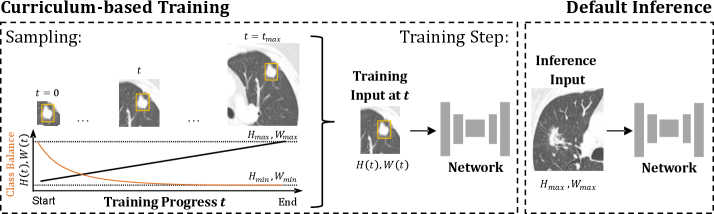

Refer to caption

Figure 1: Overview of the proposed Progressive Growing of Patch Size curriculum, illustrated for lung cancer segmentation (cancer regions highlighted with yellow bounding boxes). Training begins with the minimal patch size (Hmin,WminH_{min},W_{min}) and progressively increases the patch dimensions stepwise until the final maximal patch size (Hmax,WmaxH_{max},W_{max}) is reached. Smaller patch sizes provide a better class balance, which decreases as the patch size grows. During inference, the maximum patch size is used to capture maximal global context. Figure is adapted from [26].

Patch size increments are applied in the smallest feasible steps, with each axis adjusted independently. By gradually increasing the patch size in minimal increments, transitions between training stages are smoothed, as the segmentation tasks at successive patch sizes remain closely related. This design provides the network with a structured sequence of progressively more challenging tasks. An overview of this curriculum is illustrated in Figure 1.